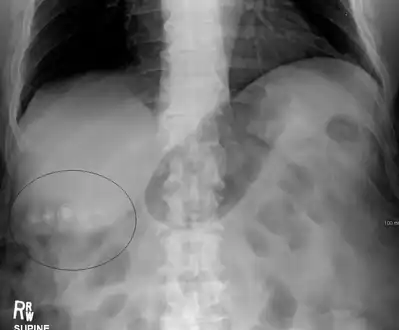

Mixed (brown pigment stones) typically contain 20–80% cholesterol (or 30–70%, according to the Japanese classification system).[38] Other common constituents are calcium carbonate, palmitate phosphate, bilirubin and other bile pigments (calcium bilirubinate, calcium palmitate and calcium stearate). Because of their calcium content, they are often radiographically visible. They typically arise secondary to infection of the biliary tract which results in the release of β-glucuronidase (by injured hepatocytes and bacteria) which hydrolyzes bilirubin glucuronides and increases the amount of unconjugated bilirubin in bile. Between 4% and 20% of stones are mixed.[3]

Biliary sludge and gallstones. There is borderline thickening of the gallbladder wall.- Gallstones as seen on plain X-ray